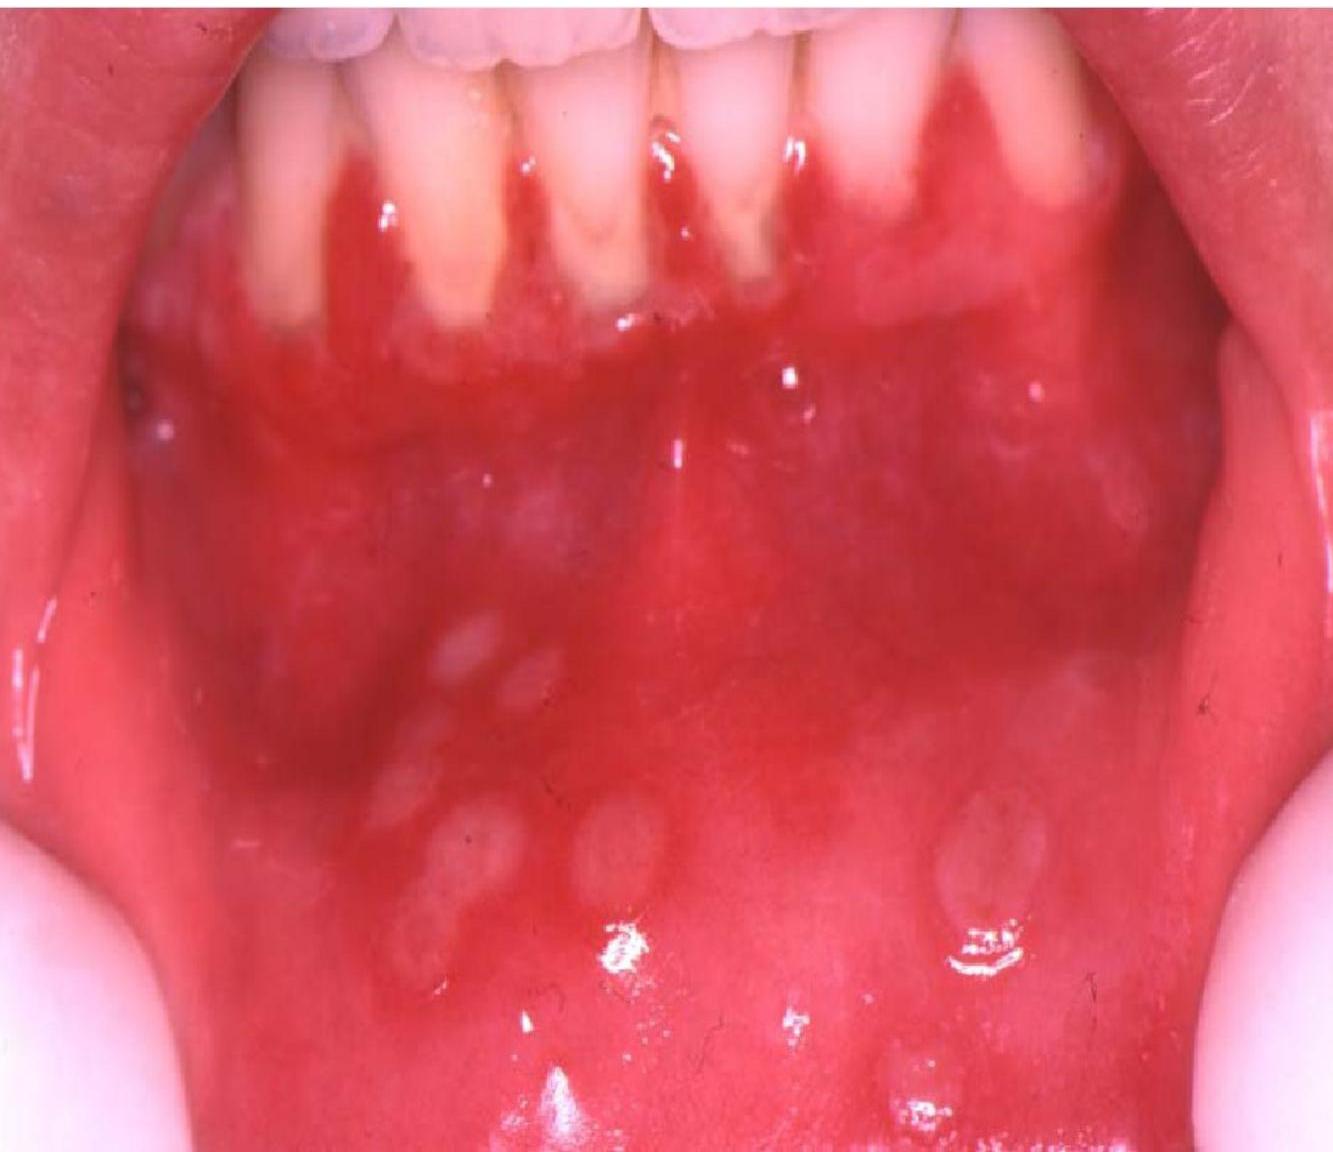

Visual Evidence - Chorioretinitis of congenital toxoplasmosis

Congenital Toxoplasmosis